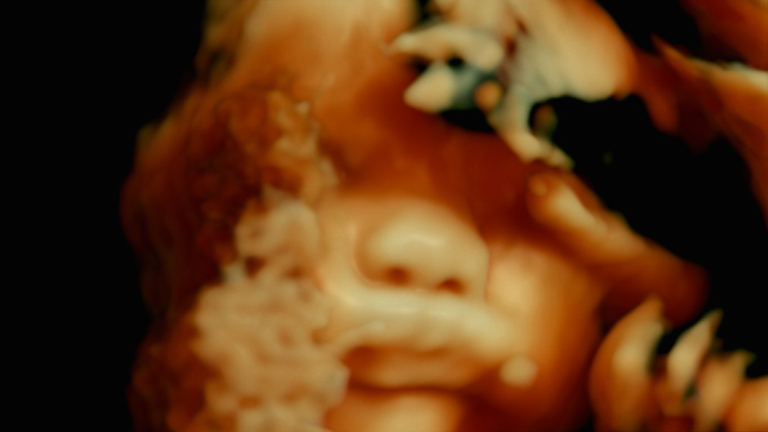

De Humani Corporis Fabrica

France - 2022 - 1H55

Il y a cinq siècles l’anatomiste André Vésale ouvrait pour la première fois le corps au regard de la science. DE HUMANI CORPORIS FABRICA ouvre aujourd’hui le corps au cinéma. On y découvre que la chair humaine est un paysage inouï qui n’existe que grâce aux regards et aux attentions des autres. Les hôpitaux, lieux de soin et de souffrance, sont des laboratoires qui relient tous les corps du monde…

Voir les séances

Le Monde : « Fait de collages d’images médicales, le documentaire de Verena Paravel et Lucien Castaing-Taylor (LEVIATHAN – 2013) ouvre des perspectives esthétiques et anthropologiques. Le corps humain palpite sous les caméras endoscopiques infiltrant ses innombrables « tuyaux » intérieurs, à la recherche d’une excroissance ou d’une cellule à éliminer. Nous voici dans les « cuisines » de l’hôpital public, au cœur de différents blocs opératoires, où les deux anthropologues ont été autorisés à filmer, ainsi qu’à télécharger l’imagerie médicale des interventions. En allant dans les « sous-sols », les réalisateurs livrent incontestablement un festin d’images, dont certaines sont propices au fantasme, à l’onirisme, même si le rêve est parfois interrompu par le bruit agressif de divers appareils médicaux (sondes, aspirateurs). Dans ces moments-là, le spectateur aura plutôt tendance à s’agripper au fauteuil comme dans un train fantôme.«